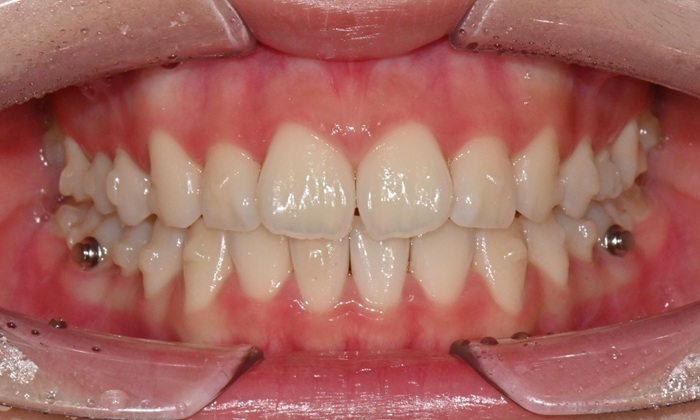

치료 시작 8개월 후 마무리 - 연세정원치과

인비절라인 컴프리헨시브 치료과정 - 연세정원치과

인비절라인 컴프리헨시브 치료 과정 - 연세정원치과

치료 후 전치부 배열이 정리되면서 웃을 때 스마일 라인도 한층 자연스럽게 개선되었습니다. 과개교합 역시 기능적으로 안정된 상태로 마무리할 수 있었습니다. 치료 후반부에 아주 경미한 중심선 차이가 남아 추가 장치를 통한 마무리를 권유드렸으나, 환자가 고2 학생으로 학업 일정이 바쁜 시기였고 현재 결과에 대해 본인과 보호자 모두 충분히 만족하여 이 상태에서 치료를 종료하기로 하였습니다.

무엇보다 이 환자는 8개월 동안의 치료 전반에 걸쳐 장치 착용을 매우 잘 지켜준 성실한 학생이었고, 그 결과 비교적 33단계의 효율적인 장치 갯수만으로도 안정적이고 만족스러운 결과를 얻을 수 있었습니다.